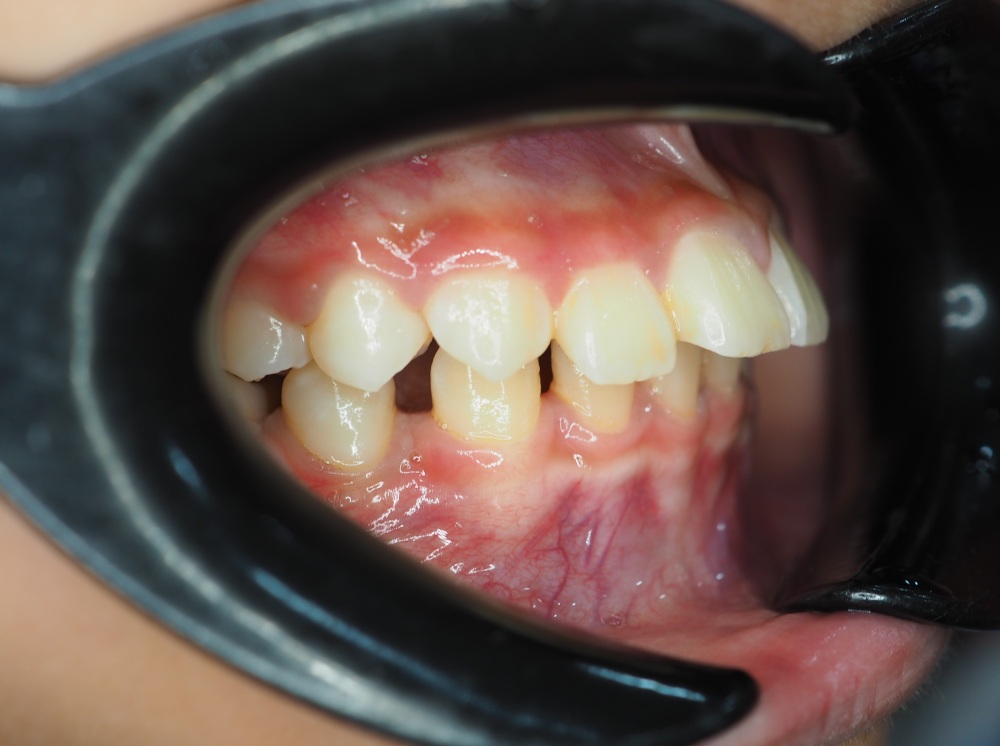

Case Study 2

Upper jaw growth → Corrected reverse bite

Age

9 years old

Parent Concern

“Her lower jaw covering upper jaw, how can Dr help with this?”

Clinical observation

Upper jaw is under-developed.

Treatment Approach

Promote mid face growth (Clear Aligner + facemask)

Treatment simulation

*side view focus on the upper jaw advancement

Treatment Outcomes

Her reverse bite was corrected in just a few months! 😁

Before (March 25)

After (Sep 25)